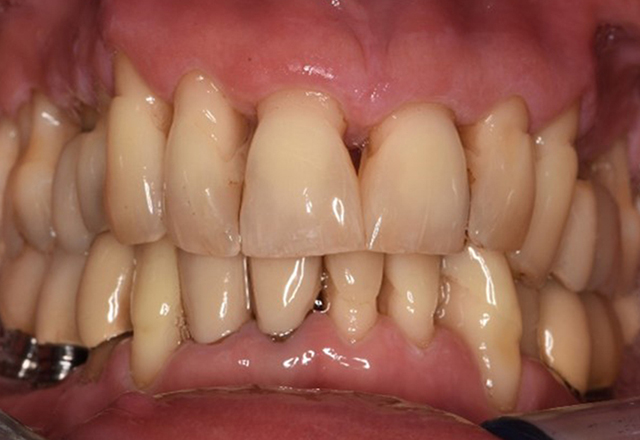

The healthy patient with early periodontal disease

The 68-year-old patient has no general health conditions and is not taking any medication that may be relevant to her oral health, and her lifestyle does not pose any particular risk. The patient has two dental implants (3rd quadrant, for five years) and a previous case of periodontal disease (stage IV, grade B periodontitis) with tooth loss. Currently the periodontal conditions are stable. However, periodontitis significantly increases the biological complications of implantations and there is a risk of implant loss (21). Four recommendations can be determined for the prophylaxis session. more